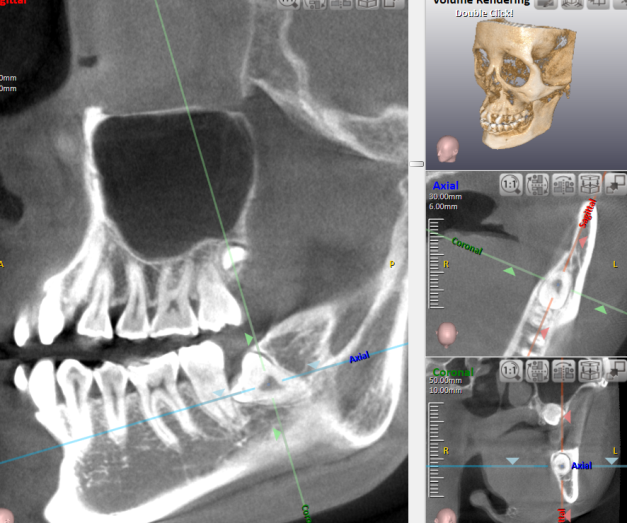

また、最新のCT機器や光学印象機器を導入しており、正確な診断と快適な治療環境が整っています。これにより、治療の負担を軽減しながら、精度の高いインプラント治療が可能です。治療後も定期的なメンテナンスを通じて、インプラントの機能と美しさを長く保つためのサポートが受けられます。

抜歯にあたっては、まずレントゲンやCTなどの画像を用いて親知らずの位置や状態を詳しく確認します。そのうえで、全身の健康状態や服用している薬などを考慮し、安全に手術を行うための準備を整えます。処置は局所麻酔を使用し、できる限り痛みや不快感を軽減するよう配慮されます。